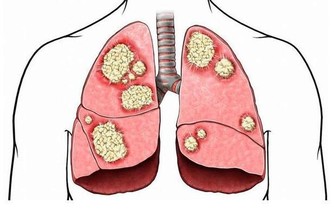

濕氣,一年四季都有。尤其在夏天,比較盛行,加上夏天氣候熱,濕氣遇熱就變成了濕熱。

濕熱重的人,最常見的體現即是會導致長痘痘,

由於濕氣會導致體內內分泌的失衡,形成臉上油膩,然後導致痘痘。